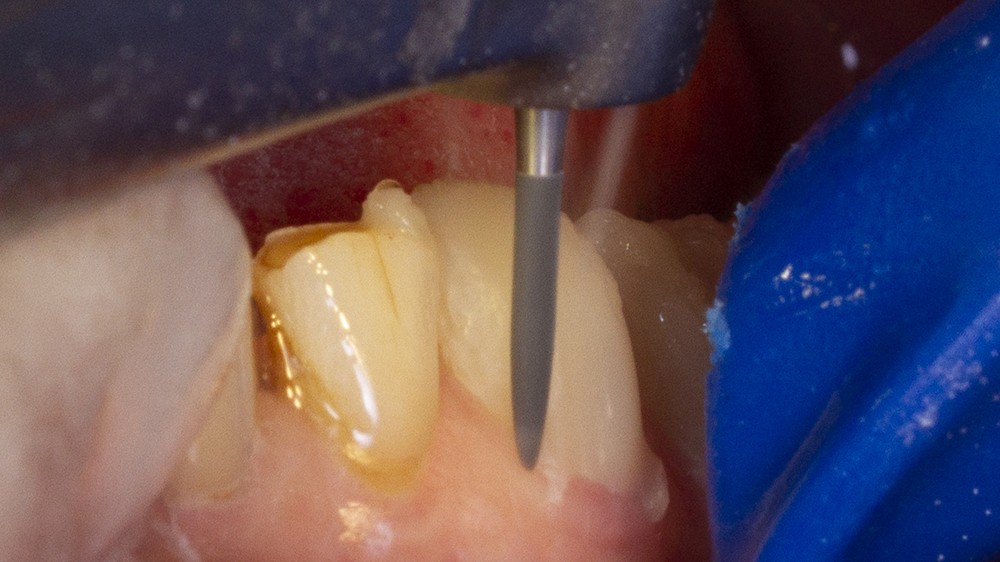

Les restaurations postérieures bénéficient également de cette technique de préparation à pénétration contrôlée grâce à l’usage de fraises spécifiques. Elles s’effectuent à travers les composites collés. Ces derniers seront intégralement éliminés ainsi que toutes les anciennes restaurations sous-jacentes afin d’assurer un collage sur des tissus optimaux.